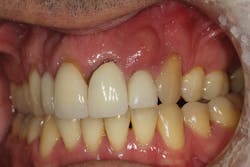

Although unpredictable, a greater amount of alveolar ridge loss following extraction usually occurs in the horizontal dimension and affects the buccal bone of the ridge.3 In fact, 50% of alveolar bone dimension can be lost after tooth extraction, with losses reported of up to 6–7 mm (figure 1). Two-thirds of this loss of bone volume can occur within the first three months of tooth extraction.4